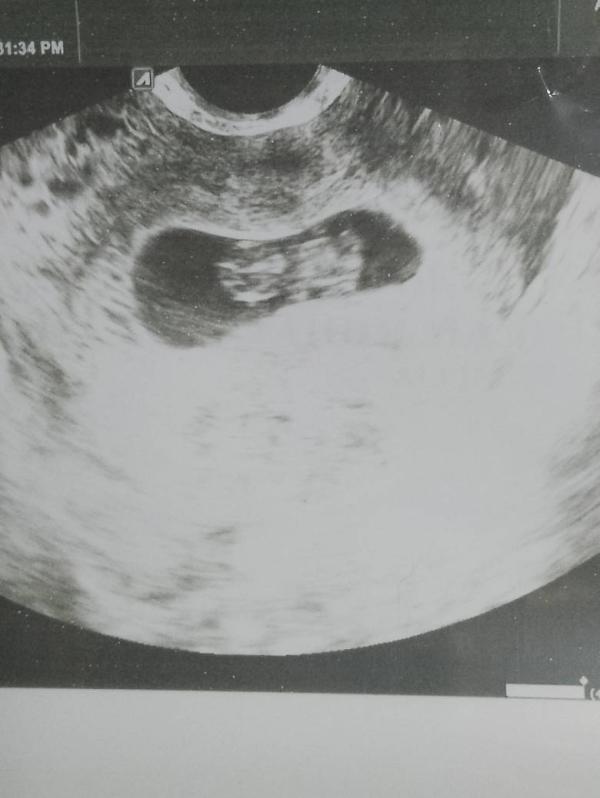

Растет мое солнышко, 8,4 дня, и уже ручки, ножки, просто чудо💋💋💋💋💋😍😍😍

Сказал все хорошо, не тонуса, ни гемотом. Но все может быть, так как волновалась когда шла очень)

Надеюсь там девочка🥰🥰🥰🥰